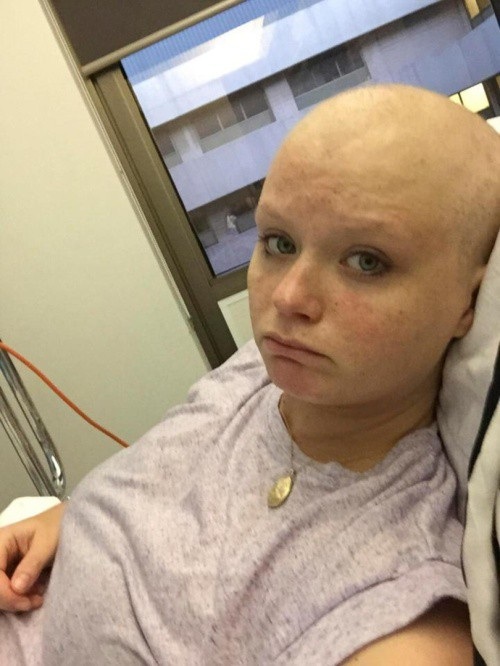

Lauren Knowles đã vô cùng hạnh phúc khi phát hiện mình sắp có em bé nhưng đến khi thai được 7 tuần rưỡi, các bác sĩ lại chẩn đoán rằng cô mắc bệnh gestational trophoblastic (bệnh lý khiến các tế bào thai trở thành tế bào ung thư).

“Khối u đã phát triển trong tử cung của tôi giống như cách mà một em bé phát triển. Hormones được sản sinh, các xét nghiệm thai kỳ ban đầu cũng được biểu hiện theo hướng tích cực. Không ai ngờ được rằng đó là ung thư cho đến khi tôi bị chảy máu và đến viện kiểm tra vào tuần thai thứ 7. Tôi đã mất tóc và 5 tháng điều trị, cuối cùng là sinh ra một khối u khổng lồ trong nhà vệ sinh”, Lauren chia sẻ.

Bà mẹ kể khối u có kích thước tương tự như một em bé 17 tuần tuổi và không thể tự đào thải ra ngoài nếu thiếu sự trợ giúp của thuốc. Các bác sĩ cũng cảnh báo Lauren rằng cô khó có thể thụ thai thêm lần nữa bởi khối u đã phá hủy tử cung. Tuy vậy bà mẹ 29 tuổi vẫn cảm thấy hết sức nhẹ nhõm vì đã thoát khỏi khối u quái ác.